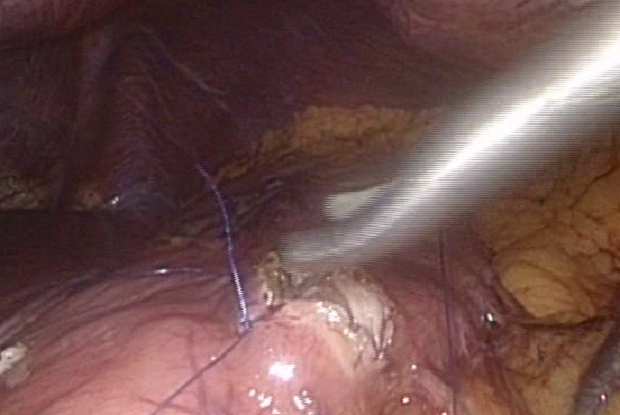

- Distal pancreatectomy (for removal of pancreas tumor)

- Cystogastrostomy/enterostomy (for removal of pancreas cyst)

- Whipple operation (for removal of pancreas cancer)